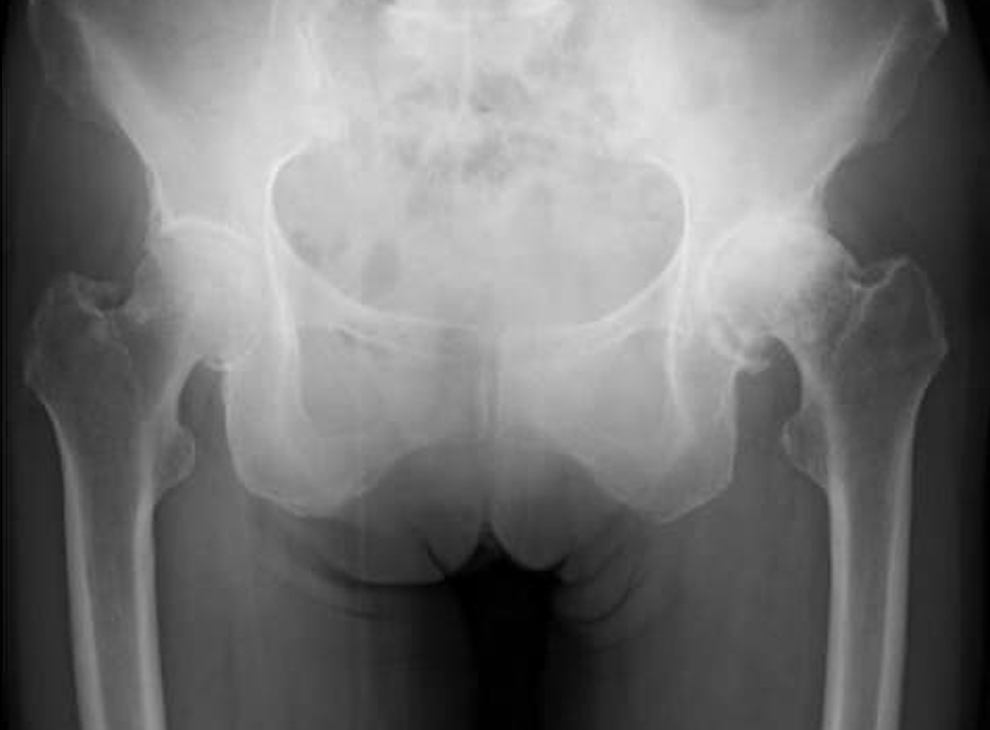

• 変形性股関節症 (術前)

• 術後のレントゲン像